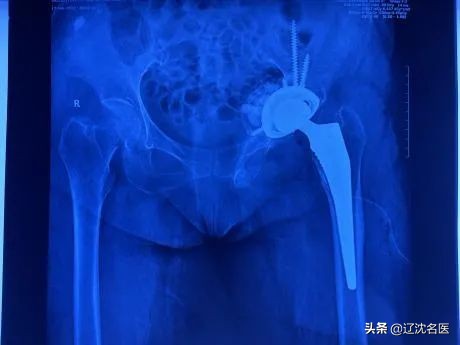

最终,在多学科的密切配合下,朴成哲主任、张斌副主任带领团队,按照术前计划以精湛的技术,极其谨慎细致地完成每一步操作,仅用2个小时,成功为孙阿姨进行了左侧髋关节置换术后翻修手术。

术后X线检查

张斌副主任介绍,像孙阿姨这种关节置换术后失败的情况临床并不多见,但一旦发生临床再次处理十分困难,因为原来正常结构完全破坏,骨质缺损严重等情况给翻修手术带来许多不确定因素。骨外一科开展3D打印技术多年,具备丰富的临床经验和娴熟的手术技术,使孙阿姨这样复杂的髋关节的翻修重建变得更加精准和安全,减少了手术时间,在提高复杂翻修手术成功率的同时,提升了患者就医感受。